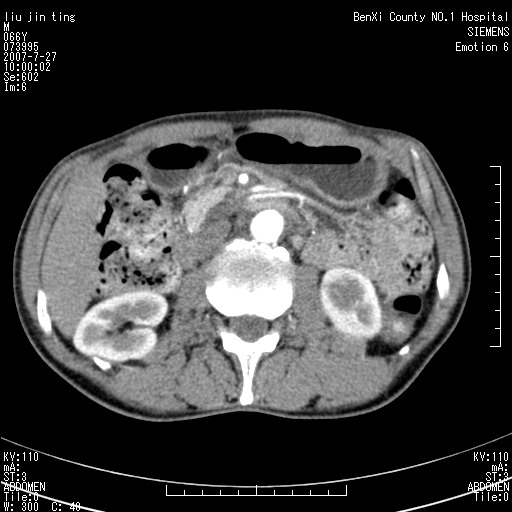

腹痛,背痛,无恶心呕吐,不黄,彩超示胰腺钩癌,ct扫描病灶平扫30-40hu,增强后动脉期40--60hu,静脉期50-68hu,真的是钩突上的么?您要试一试么?

动脉期

静脉期

沿着肠系膜上动脉呈匍匐性生长的软组织肿块,形态不规则,包绕肠系膜上动脉,呈明显强化,考虑来源于肠系膜的恶性肿瘤

沿着肠系膜上动脉呈匍匐性生长的软组织肿块,形态不规则,包绕肠系膜上动脉,呈轻-中度强化,考虑来源于肠系膜的恶性肿瘤。

钩突是正常的,只见腹膜后淋巴结的肿大,考虑淋巴瘤或转移可能。

支持!恶性纤维组织细胞瘤可能,与淋巴瘤及淋巴结转移鉴别(腹主动脉周围清晰,其他部位亦未见明显肿大淋巴结)。